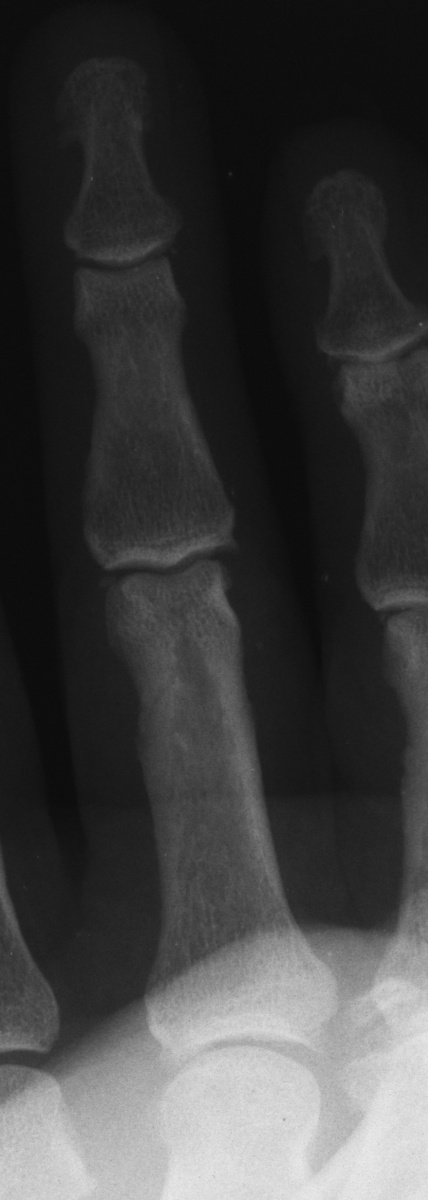

However, an AP view with the proximal phalanx flat against the plate perpendicular to the beam shows prominent proximal phalanx osteophytes, one of which has caught one of the collateral ligaments.

Closed manipulation was performed with a median nerve block, rotating the proximal phalanx through pronation and supination while applying longitudinal distraction in the direction of the deformity. Click on the image below for a video of the reduction.